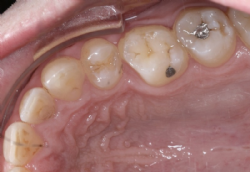

Behandlung in Kombination mit Zahnextraktionen

Gar nicht so selten ist die Anzahl der vorhandenen bleibenden Zähne größer als es dem Platzangebot des Kiefers entspricht. In diesen Fällen ist die Entfernung bleibender Zähne oft die einzig zielführende Möglichkeit, harmonische und schöne Zahnreihen zu erhalten. Entfernt werden jene Zähne, deren funktionelle Wichtigkeit relativ am geringsten ist, unter Berücksichtigung etwa vorhandener (behandelter oder unbehandelter) Karies, sowie der geplanten Zahnbewegungen.

Bei geringem Platzmangel kann stattdessen auch die Verschmälerung mehrerer bleibender Zähne des betreffenden Kiefers durchgeführt werden (Approximale Schmelzreduktion, „Stripping"). Dabei werden die Zähne an ihren jeweiligen Berührungsflächen mit geeigneten Instrumenten (feine rotierende Instrumente oder abrasive Streifen) bearbeitet und geringfügig Substanz reduziert.